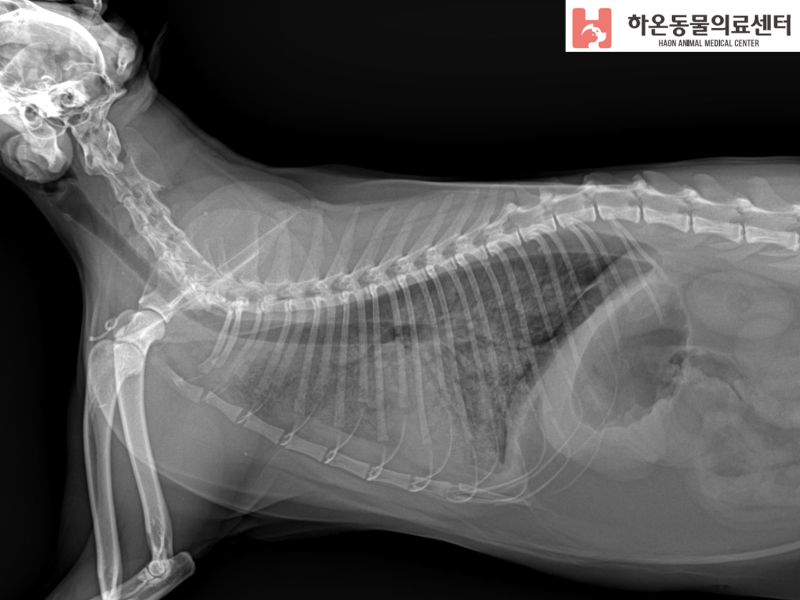

울혈성 폐부종을 일으킬 수 있는 심장 상태에는 비대성 심근병증, 확장성 심근병증, 승모판 부전 및 울혈성 좌심부전을 일으킬 수 있는 기타 상태가 포함됩니다. 진단 및 치료심장성 폐부종과 비상피성 폐부종을 감별하기 위해서는 심초음파를 통한 정확한 심장 평가가 필요하다. 심한 기침, 빠른 호흡, 강제호흡, 강아지의 눈에 청색증 등의 증상이 나타난다면 폐부종의 가능성이 있으니 급히 동물병원에 내원하여 관련 치료를 받아야 합니다. 강아지가 호흡 곤란이나 청색증을 보이면 동물 병원을 방문해야 합니다. 동물병원에서는 산소를 공급받으면서 호흡을 안정시키는 것을 최우선으로 하고 이뇨제를 투여하여 폐의 냉수를 제거한다. 그 후 2~3일간 입원하여 필요한 치료를 진행하며 폐 침윤을 확인하고 경과를 관찰한다. 강아지 호흡곤란 환자의 CPE 실례 중성화된 8세 암컷 말티즈 H는 지난해 9월 심장병 MMVD B2 진단을 받고 관리를 받고 있다. 내원 전날 저녁부터 무기력감과 호흡곤란을 보였다. 환자가 호흡곤란을 주증상으로 해마루동물병원에 내원하였다. 환자는 심장약을 복용하지 않았으며 흉부 방사선 사진에서 폐 침윤이 확인되었습니다. 흉부 방사선 사진에서 폐 침윤이 확인되었다. 내원 당시 가쁜 호흡이 관찰되었고 청진상 심잡음이 확인되어 응급처치로 산소공급과 이뇨제 주입을 시행하였다. 호흡이 안정화된 후 흉부 X-선에서 좌심실 비대와 폐야 전체에 침윤이 관찰되었다. 이것은 확인되었습니다. 심초음파 소견상 이첨판 비후와 좌심방 비대 소견을 보였고 혈액 역류가 심한 상태였다. 또한 좌심방의 압력이 분명히 높아졌습니다. 호흡곤란이 있는 개 환자의 심초음파는 다른 혈액 검사에서 염증 수치가 약간 증가한 것 외에는 특별한 소견을 보이지 않았습니다. 환자의 병력과 종합검진 결과를 종합적으로 고려할 때 울혈성폐부종(CPE)으로 진단받았다. 혈액검사 결과 CRP가 약간 증가한 것을 확인하였다. 이에 환자는 진단 결과 저희 병원 중환자실에 입원하여 심인성 폐부종으로 집중 치료를 받기로 결정하였습니다. 확진 후 환자는 무사히 퇴원할 수 있었다. 입원을 통해 폐 침윤이 소실된 것을 확인하였다. 환자는 심장약을 복용한 이력이 없었다. 임상 증상 및 현재 진단 결과를 바탕으로 외래 진료를 통한 장기 관리 및 추적 관리를 위해 경구용 약물을 계속 복용하기로 결정하였습니다. 내과 재검사에서 유의한 폐 침윤은 확인되지 않았으며, CRP(염증 수치)는 정상이었으며, 신장 수치도 호전된 것으로 확인되었다. 청진 중인 말티즈 환자 오늘은 심장병 관리 중 급성 호흡곤란으로 응급병원을 찾은 심인성 폐부종 강아지 사연을 만나봤습니다! 빠른 호흡, 입을 벌리고 호흡하는 것, 혀가 파래지는 청색증 등 호흡 불안정을 경험한다면! 빠르게 동물병원에 내원하여 호흡을 안정시키고 원인을 찾아 적절한 치료를 받아야 합니다. 해마루동물병원은 24시간 특화된 응급진료와 더불어 밤낮으로 집중 치료가 필요한 아픈 개, 고양이 환자들을 저희만의 중환자 관리 시스템을 통해 치료하고 있습니다. 또한 진료과별 외래진료소와의 원스톱 협력체계를 통해 환자에게 가장 적합한 진료서비스를 제공하고 있습니다. 하다. ▼ 더 많은 의료사례 보러가기 ▼ 강아지 폐부종. 강아지의 호흡수가 빠르다면! “강아지 호두(가명)는 심장병이 있지만 임상 증상이 없는 ACVIM B2기 진단을 받고 심장약을 먹었습니다… 폐부종 심장성 폐부종은 심장의 이상, 즉 박출 기능 장애 및 역류로 나타납니다. 개의 다양한 심장병에 나타나… 병원 #강아지심장내과 #강아지응급상황 #강아지응급실 #강아지내과 #성남24시동물병원 #분당24시동물병원 #2차동물병원 #다학제클리닉 #해마루동물병원 #해마루1차동물병원 #해마루응급중환자 케어 센터